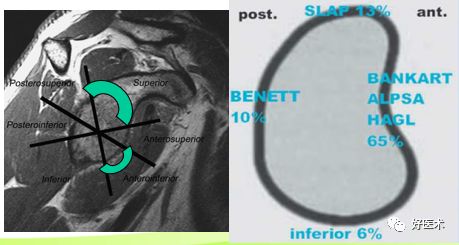

盂唇损伤要点

程度:磨损、撕裂

-

部位:上、前上、前下、下、后下、后上

以SLAP损伤(上)和Bankart损伤(前下)最常见